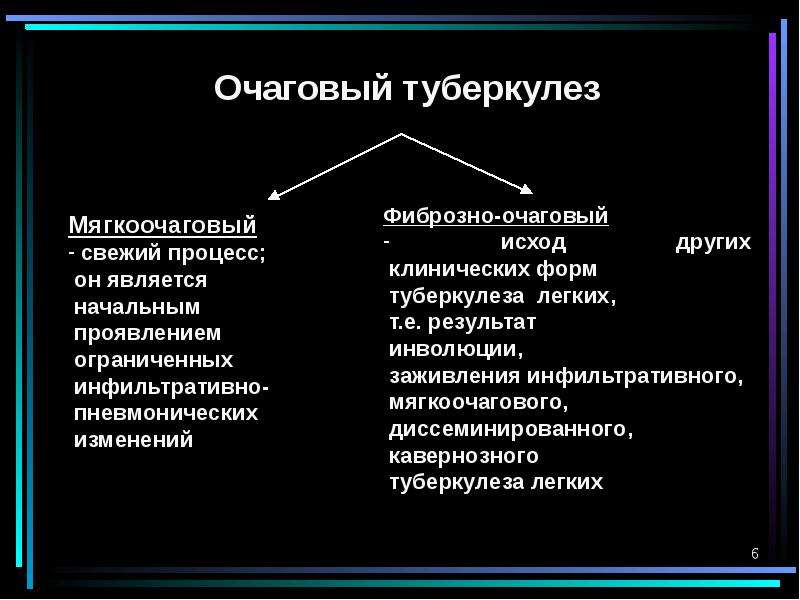

Очаговый и инфильтративный туберкулез презентация - 94 фото